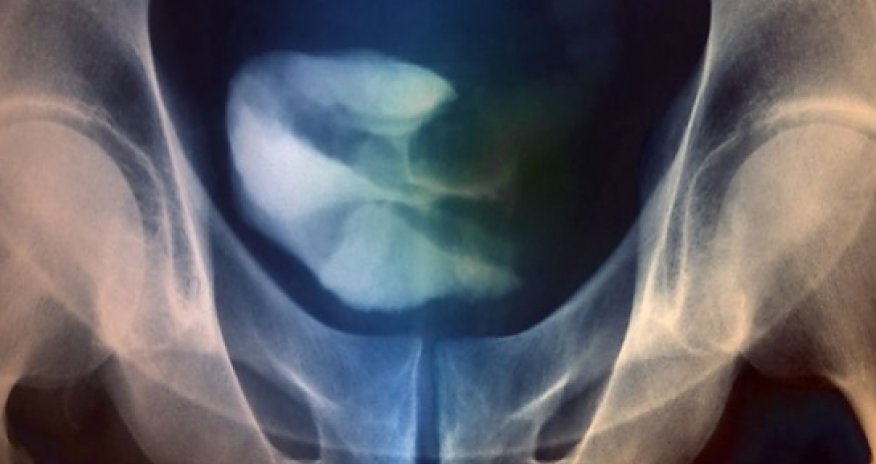

Bladder cancer: 'Exciting' drug breakthrough

It strips cancer cells of the "camouflage" they use to evade attack by the immune system.In the most detailed study, published in Nature, some patients completely recovered from terminal bladder cancer.Cancer Research UK said the field of immunotherapy was delivering "a lot of very exciting results".The immune system is in delicate balance with some chemicals in the body encouraging a strong vigorous response, while others try to dampen it down.Tumours can hijack this system to hide from the immune system.One trick which tumours use is a protein called PD-L1 which is normally used to prevent autoimmune diseases.BladderAn international team of scientists has been trialling a drug to block PD-L1, produced by the company Roche, on 68 people with advanced bladder cancer.All the patients had tried chemotherapy and had been given six-to-eight months to live.More than half the patients, whose tumours were using PD-L1 to hide from the immune system, showed signs of recovery.In two patients there were no signs of cancer after the treatment.One in ten patients responded to the experimental therapy even if PD-L1 was not present in the tumour.Dr Tom Powles, an oncologist at the Barts Cancer Institute at Queen Mary University of London and part of the research team, said "There have been no new drugs for bladder cancer for 30 years."The tumours have developed a camouflage layer, PD-L1, and by removing the camouflage the tumour becomes identifiable."A subgroup of patients seems to do exceptionally well."Dr Powles is funded by the NHS and receives no money from Roche.The drug has been given "breakthrough therapy" status in the US and could be used widely by patients there at the end of 2015, if a larger trial shows the same results.Much larger randomised clinical trials would be needed in order for the experimental therapy to be used in Europe.More cancersDr Roy Herbst, who led the research at the Yale Cancer Centre, told the BBC: "This is a new paradigm in cancer."Immunotherapy for cancer has opened up an entirely new modality for treatment of the disease alongside chemotherapy, radiotherapy and surgery."Now we have immunotherapy and it is here to stay and the challenge for clinicians is seeing how it fits alongside those others."His study was focused on the environment around a tumour and immune cells there, in order to help predict which patients would respond to therapy.A similar set of trials to boost the immune attack revealed at the American Society of Clinical Oncology conference in Chicago in June, showed similar therapies could improve survival in advanced skin cancer.In a trial of 411 patients evaluating a drug, pembrolizumab - 69% of patients survived at least a year.Those results were described as having the "potential to be a paradigm shift for cancer therapy".A separate study of 175 patients, led by Yale University in the US, showed responses to the drug in patients with non-small cell lung cancer, melanoma, renal cell carcinoma and other cancers.Prof Peter Johnson, the chief clinician at Cancer Research UK, said: "We're seeing a lot of very exciting results from these new treatments using the immune system."This study in bladder cancer is further proof of the power of this approach, and it's really good to find a new treatment for a type of cancer that we've been struggling to make progress with for many years."Bakudaily.Az